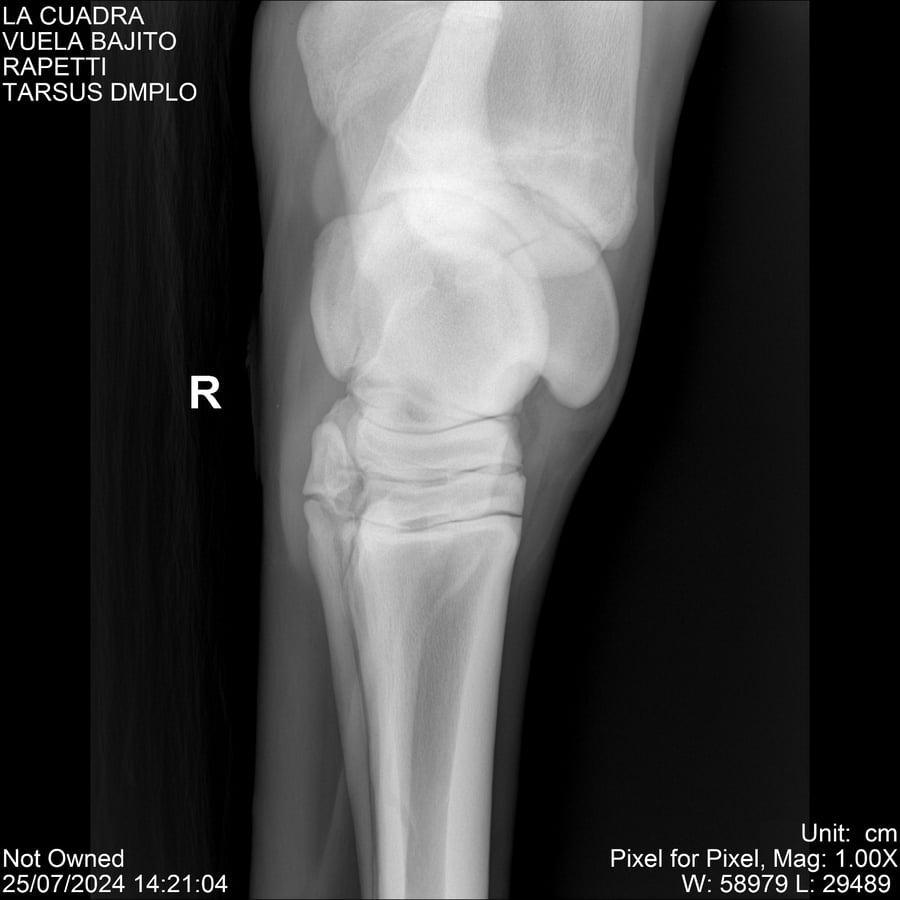

LOTE 16, VUELA BAJITO Lote Anterior Volver al remate Lote Siguiente Ficha Contacto Montevideo - Ficha del Lote Identificador: #284451 Categoría: Yeguarizos Montevideo - 77 Visualizaciones ClicData Contacto Empresa: Abelenda N. R., Walter Hugo Nombre*: Teléfono* : E-mail* : Mensaje Enviar Registrese gratis Este contenido Exclusivo está disponible sólo para usuarios registrados Ingresar